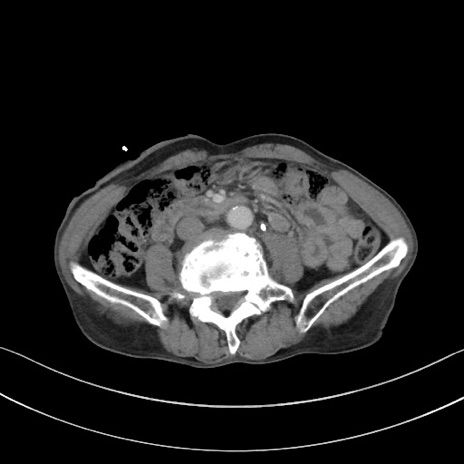

症例3(横断像)

【症例】 70歳代男性

【主訴】右鼠径部腫瘤、疼痛

【現病歴】本日朝より上記主訴あり、受診。

【既往歴】膀胱癌にて膀胱全摘、両側尿管皮膚瘻

【データ】WBC 5600、CRP 0.56